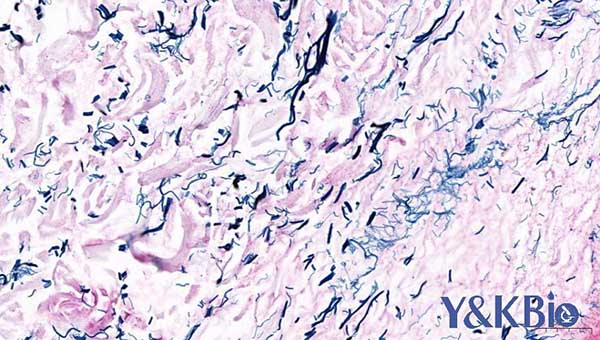

一、MASSON染色

适用于所有动物组织, 常用于胶原纤维染色

染色结果: 胶原纤维呈蓝色,肌纤维、和红细胞呈红色。